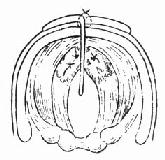

4.手术方法 基底在舌骨水平的弧形切口,皮瓣包括颈阔肌被翻转向上。常规甲状软骨正中垂直裂开术。3-0线缝合声带粘膜裂口后,褥式缝合声带及室带使其与同侧甲状软骨板靠拢(图96-7)。对合复位骨折的甲状软骨板并用丝线缝合甲状软骨外板软骨膜。自甲状软骨板裂开术正中切口处,放入钽片,使其位于双声带前端之间前连合处,分开双侧声带,防止喉蹼形成,用钢丝将钽片固定在甲状软骨板上,缝合甲状软骨板正中切口处之外板软骨膜(图96-8)。逐层缝合切口。

图96-7 声门损伤手术方法

图96-8 甲状软骨板中置钽片